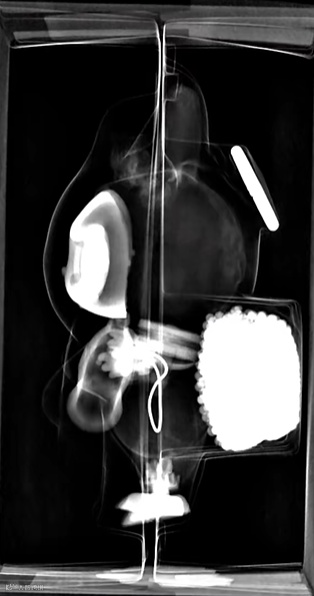

放射科DR检查室内,一个咧嘴大笑的Labubu玩偶,被轻轻摆上检查台,它即将迎来一次医学上的曝光。

X射线穿过搪胶外壳,仪器嗡鸣声中,Labubu的黑白影像逐渐清晰:层叠交错的合金 “支架” 如微型脊椎般贯穿躯干,磁吸关节在屏幕上泛着冷光,胸腹腔处一片刻意留白的空洞,仿佛在吞吐情绪。

此图一出,网友辣评:布布一点骨气都没有